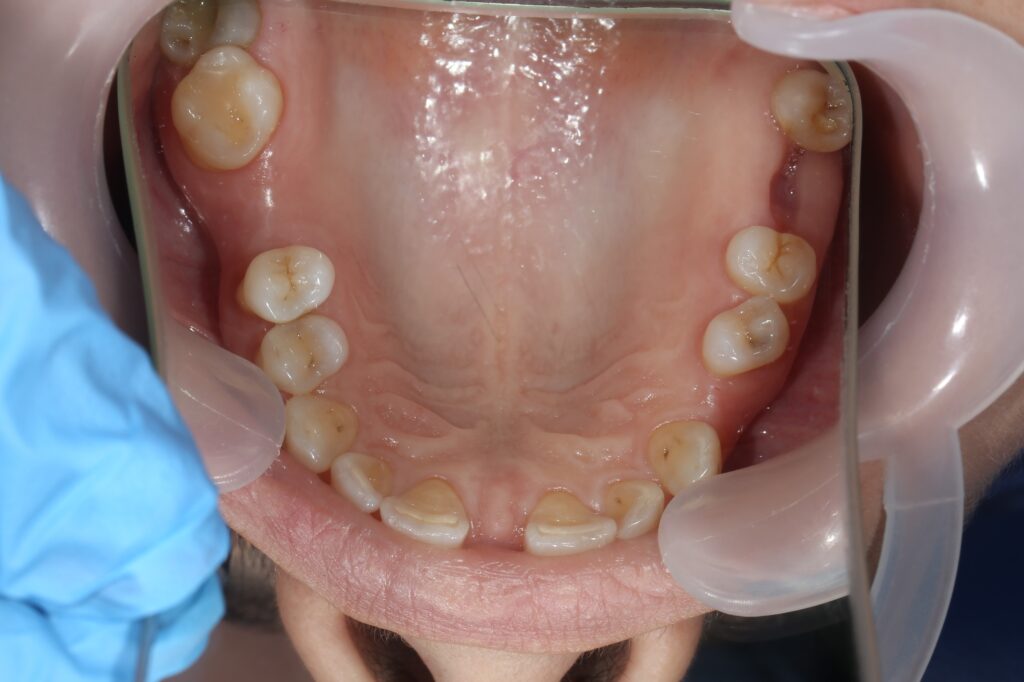

Ситуация до лечения

Пациентка 39 лет была направлена стоматологом-ортопедом для ортодонтической подготовки перед протезированием.

Из-за множественных давних удалений жевательных зубов, произошла деформация зубных рядов, зубы разъехались в область удаленных, что затрудняло протезирование в момент обращения к ортопеду.

Так же можно отметить сильное снижение высоты прикуса (верхние зубы на 100% перекрывали нижние, что вызывало хроническую травму десны), а также повышенную стираемость твердых тканей зубов,

что является следствием повышенной нагрузки, которую много лет испытывали передние зубы, в связи с отсутствием жевательных зубов.

пациент до брекетов